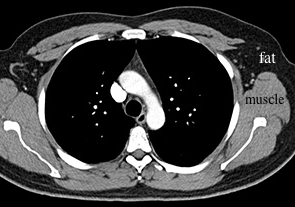

BONE window-notice that you can see a central marrow cavity that is lower attenuation than the outer cortex in every bone on the image. Notice that fat and muscle are similar shades of grey.

All three of these images show the exact same data, with different brightness and contrast settings. There are other special CT windows for brain, liver and contrast material.